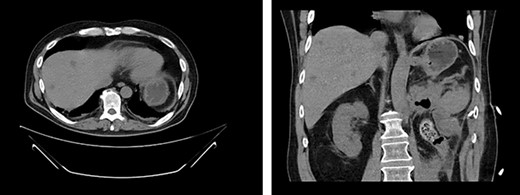

First appearance of multiple liver lesions suspicious for metastasis in transverse (left) and coronal (right) planes on CT; reduction of retroperitoneal effusion can also be seen.

Serial CT scans at 10 and 12 weeks post-resection revealed reduction of the retroperitoneal abscess and appearance of liver lesions concerning for metastasis (Fig. 4). The patient eventually completed his radiation course with no additional problems.